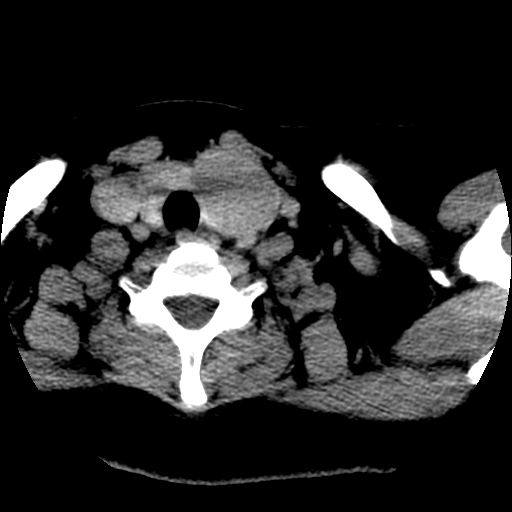

标题: CT25491:女,55岁,发现左侧甲状腺肿块一个月。 [打印本页]

女,55岁,发现左侧甲状腺肿块一个月,彩超示:甲状腺多发结节伴左叶结节液化。

左右叶都有,峡部也受累,有钙化,考虑结甲可能性大。

考虑右叶结节性甲状腺肿,伴左叶钙化。主要(1)密度均匀,边境清。(2)病灶与血管界限清。